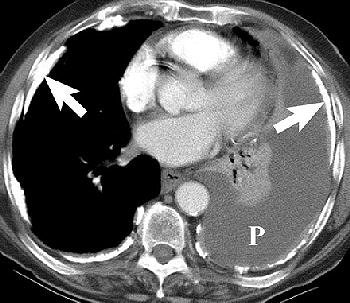

Pleural effusion in a 70-year-old man with a history of asbestos exposure and known left-sided MPM. Axial contrast-enhanced CT scans obtained at different levels show unilateral pleural effusion (P, above) with extensive calcified pleural plaques (arrows, below). Figure 1a-b, Wang ZJ, Reddy GP, et al, "Malignant Pleural Mesothelioma: Evaluation with CT, MR Imaging, and PET" (RadioGraphics 2004; 24: 105-119).

According to the results, asbestosis was suggested in 64% of the cases based on the semiquantitative CT severity score. With the cumulative scoring method (based on multiple CT features), any one type of abnormality was found in 88 instances.

"However, to include only cases with asbestosis, three different abnormalities had to be present," they wrote. "The high-resolution CT scans were normal or near normal in five instances of asbestosis. Chest radiographs using the ILO classification predicted asbestosis with a less frequency than ... CT," (AJR, January 1995, Vol. 164:1, pp. 63-68).